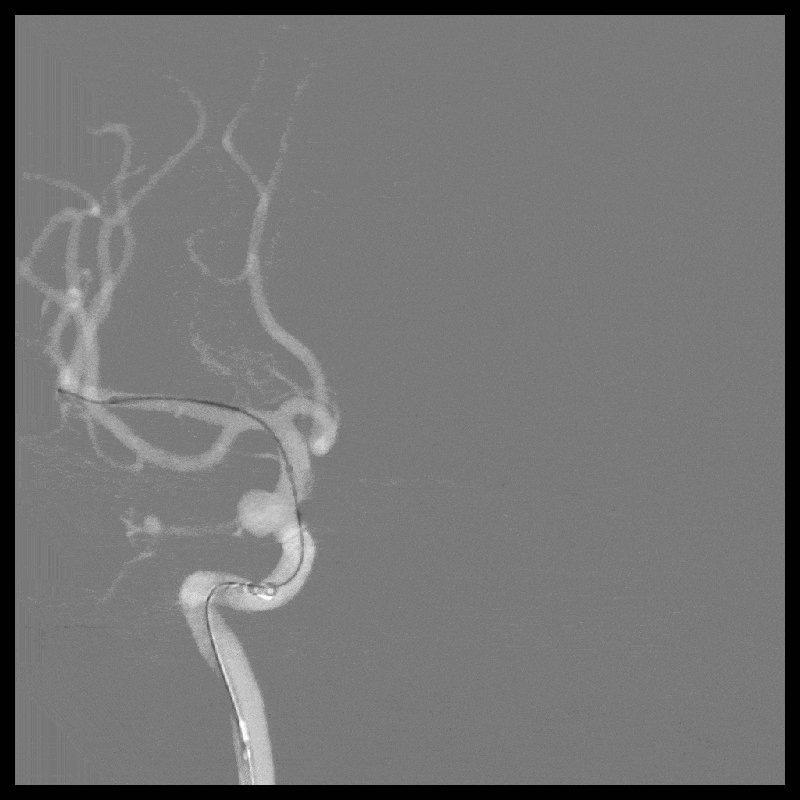

2021-12-20 脑血管造影:

左侧颈内动脉多发动脉瘤;右侧颈内动脉床突段动脉瘤。

LICA 多发动脉瘤,大小分别为3.09×3.79mm、1.73×1.73m及1.79mm×1.63mm,载瘤动脉远端直径为3.11mm,近端直径3.49mm。

RICA 床突旁动脉瘤 6.56×5.29mm ,载瘤动脉近段直径约3.66mm,远端直径3.40mm。

2021-12-24 左侧颈内动脉血流导向装置重建术(Tubridge)

L-ICA血流导向装置(Tubridge 3.5*25mm)。